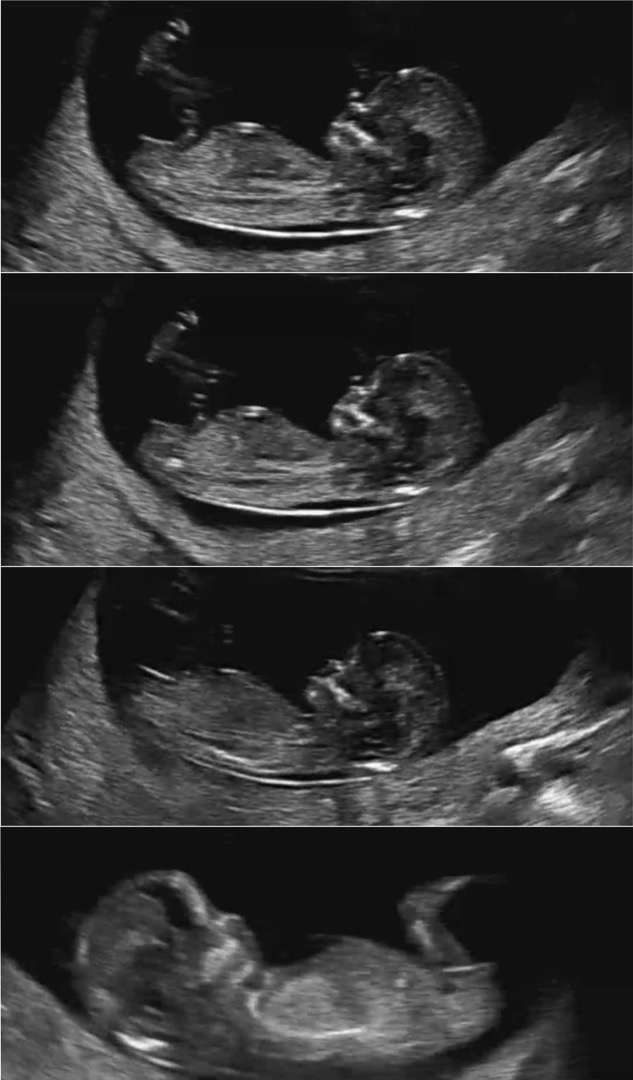

각도법고수 계신가요? 아들일지 딸일지 궁금해요 12주3일 입니다아ㅏ🍀

의견 마구마구 부탁드려요!

딸이요👧🏻